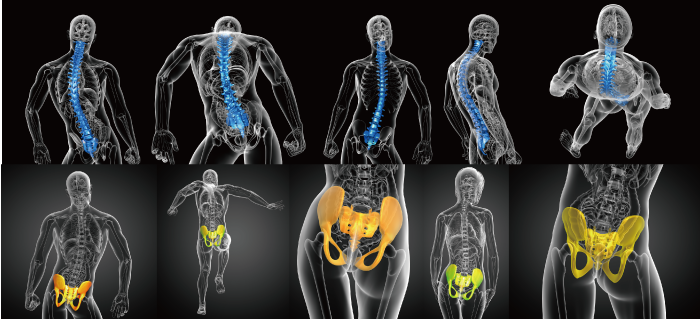

尰嵼傾僠乕僽偺3杮拰亂偹偠傟挷惍亃亂俁D憿婄亃亂俁D僆乕儖僀儞儚儞僩儕乕僩儊儞僩亃偼

10擭娫偺廤戝惉偱偡丅